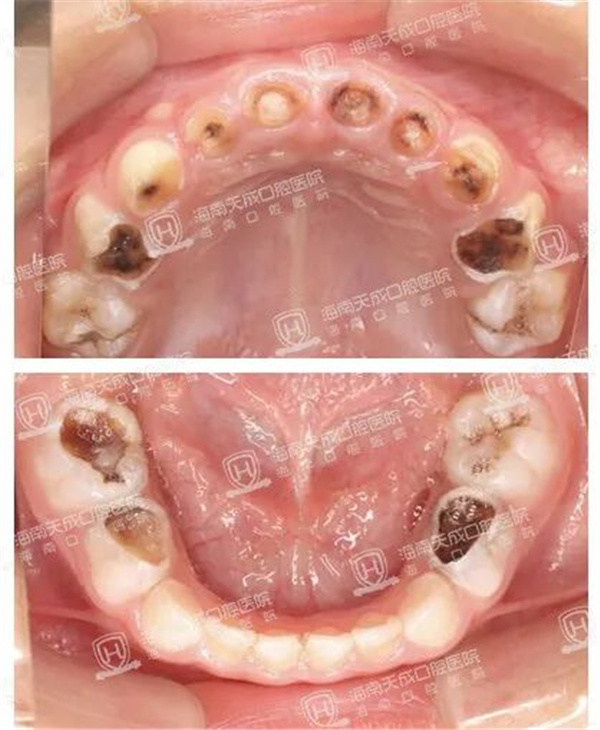

年仅 2岁11个月 的恺恺(化名)全口20颗乳牙竟蛀坏了18颗上前牙有5颗牙齿仅剩残根8颗大牙严重龋坏,常出现牙疼症状

全口20颗乳牙有18颗牙齿存在不同程度的龋坏(蛀牙),另外2颗牙齿表面也出现脱矿(蛀牙的前期阶段)。其中,上前牙有5颗牙齿仅剩残根,8颗大牙严重龋坏,多颗牙齿已露髓(牙神经),出现自发牙疼症状。